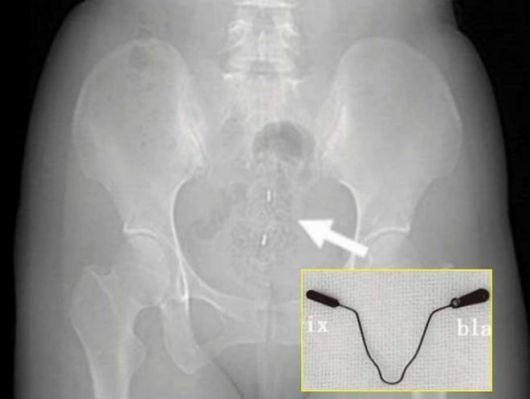

검사 결과 환자의 몸에서는 2년 전 삽입한 피임 장치가 자궁을 관통해 방광 후벽을 파고든 상태였다.

방광에서 발견된 피임 장치는 본래 자궁 안에 넣는 ‘자궁 내 장치’(IUD)로 5~10분 만에 간단한 시술로 끝나고 99% 이상 높은 피임 성공률을 보여 전 세계에서 널리 사용되는 피임 방법이다.

그러나 자궁 내 장치가 자궁을 관통해 방광까지 침투하는 ‘자궁 천공’ 현상은 매우 드문 것으로 알려졌다.

피임 기구가 자궁을 뚫고 방광까지 침투한 사례. 큐레우스 제공 |